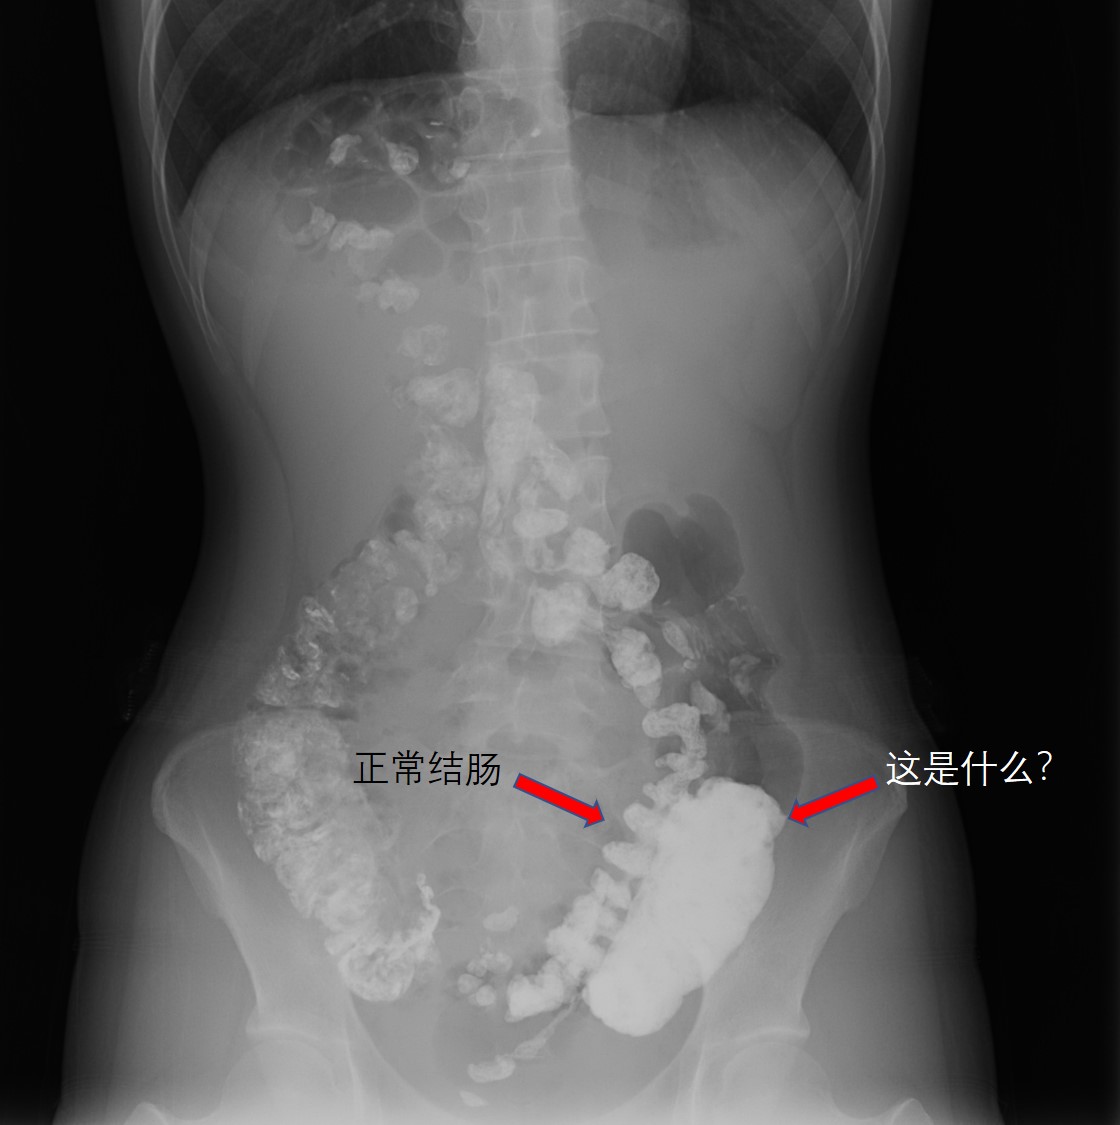

近期我们收治了一个特殊的患者。她与大便斗争了12年了,总是左下腹痛腹胀排便排不出来。口服了各种通便的药物,也吃遍了各种蔬菜水果,但是效果欠佳。经过消化道造影的检查我们发现结肠是这样的:

正常结肠旁边多处一节?

腹平片、腹部CT以及肠镜等检查有助于结肠重复畸形诊断[3]。腹平片有助于结肠重复畸形的诊断和鉴别诊断;腹部CT可明确畸形部位及其与周围肠管的解剖关系;与囊状畸形不同,管状畸形结肠与正常肠管之间有共同开口,肠镜对这种畸形诊断价值较大。本例患者术前腹平片和CT均提示重复结肠。